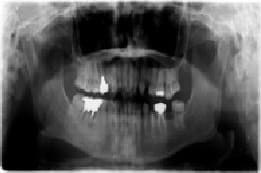

レントゲンで歯を支えている骨の状態を確認し、必要があればCT撮影します。

レントゲン